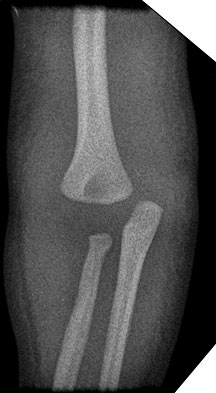

The ages at which the elbow ossification centers appear are highly variable.